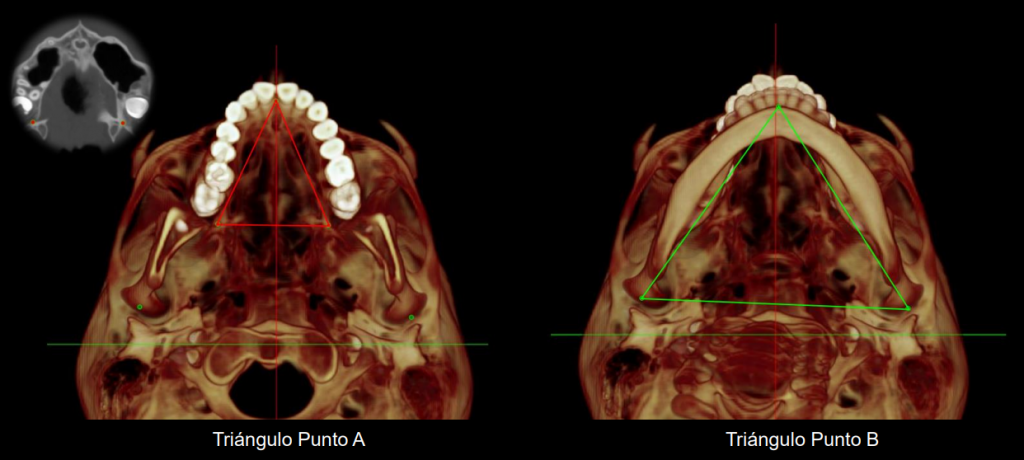

Estudios Personalizados

Cada paciente y cada tratamiento es único. El profundo conocimiento de la anatomía y de nuestros pacientes junto con la tecnología más avanzada nos permite realizar diagnósticos certeros. Localizando el origen del problema muchas veces incluso antes de que se produzca evitando así su aparición.